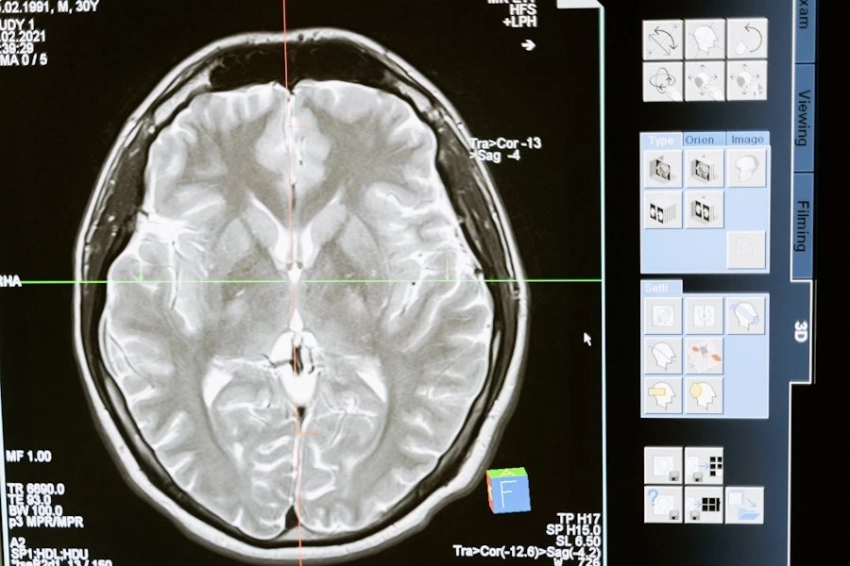

Как сообщает журнал Nature Communications, выводы учеными были сделаны на основе анализа данных, полученных при сканировании мозга. В группе добровольцев была категория людей, демонстрировавших повышенный уровень тревожности.

Тот и другой будут слегка взволнованы встречей. Но, как показало сканирование, у тревожных людей при этом включается иной участок мозга, мало подходящий для подобных коммуникаций. Поэтому им и так сложно решаться на общение в социальной среде.

Участникам эксперимента предлагали выбирать на экране изображения лиц. Сначала счастливые, радостные, потом — угрюмые, строгие. Справлялись с задачей все примерно одинаково, но у людей, подверженных тревоге, при этом активировался не передний отдел префронтальной коры, логичный в данном алгоритме, а один из соседних участков. Это открытие, надеются ученые, поможет искать новые методы лечения депрессии и тревожности.